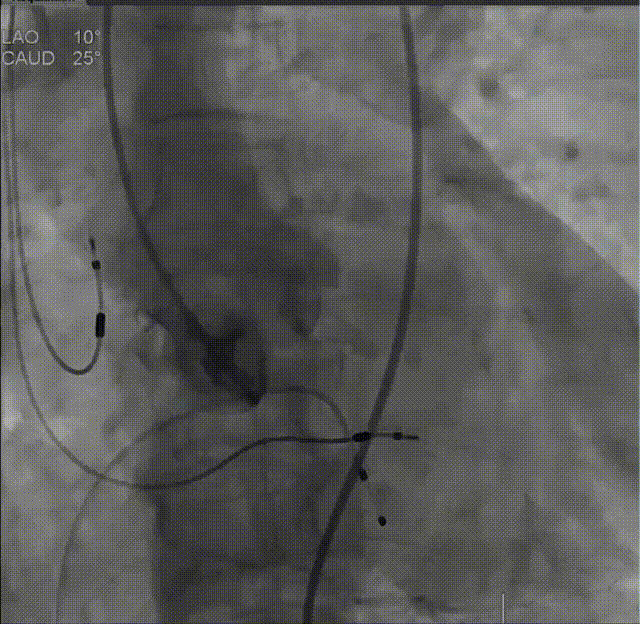

根部造影,导管测压70mmHg

球囊预扩,无腰征,无漏,考虑常规sizing,选用29mm THV

瓣膜在瓣环下精准定位,稳定释放